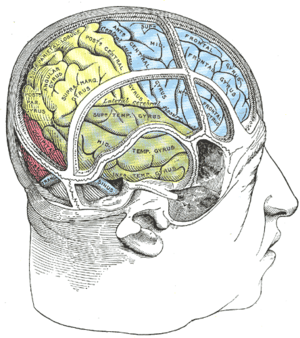

Coronal section through anterior cornua of lateral ventricles. Inferior frontal gyrus is shown in yellow. Drawing to illustrate the relations of the brain to the skull.

Drawing to illustrate the relations of the brain to the skull. Lateral view of a human brain, main gyri labeled.